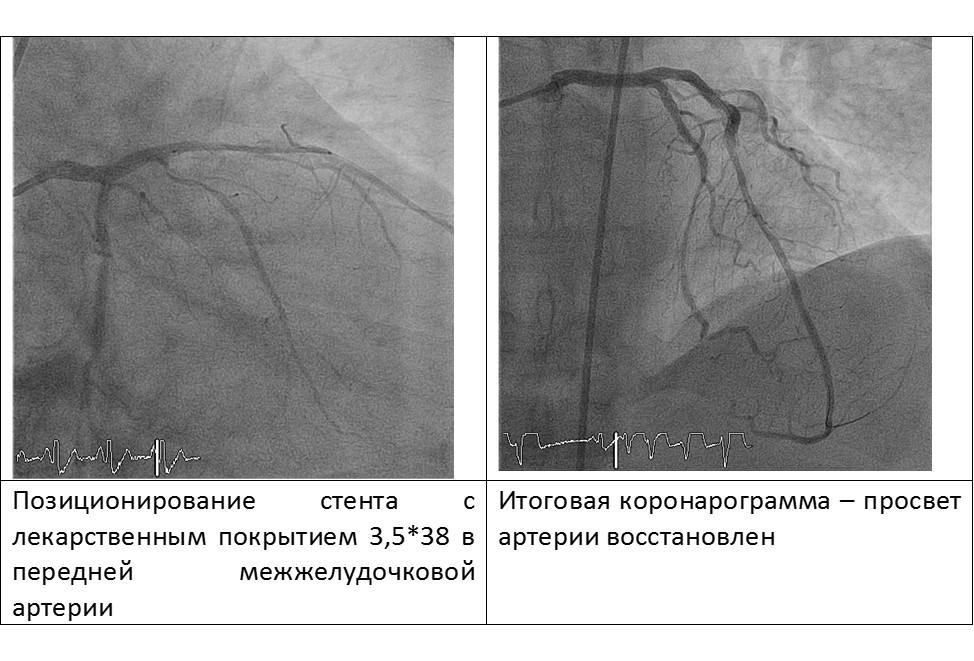

С помощью микрокатетера «найден» истинный просвет ПМЖВ, выполнена баллонная ангиопластика и стентирование передней межжелудочковой артерии DES 3.5*38mm.

Пациент выписан на седьмые сутки после операции в удовлетворительном состоянии.

Диагноз при выписке: ИБС, о.,с подъемом ST Q-необразующий передне-боковой ИМ ЛЖ от 02.06.2016 (IV a тип). КАГ 02.06.2016, ЧТБА и стентирование ПМЖВ DES 02.06.2016, состояние после ЧКВ ОВ 07.2015.